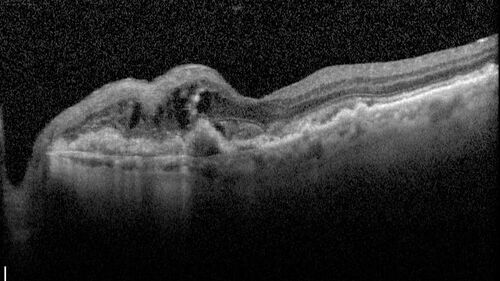

Idiopathic Polypoidal Choroidal Vasculopathy

83 year old man with wet AMD for 12 years resistant to Anti-VEGF therapy but responsive to PDT